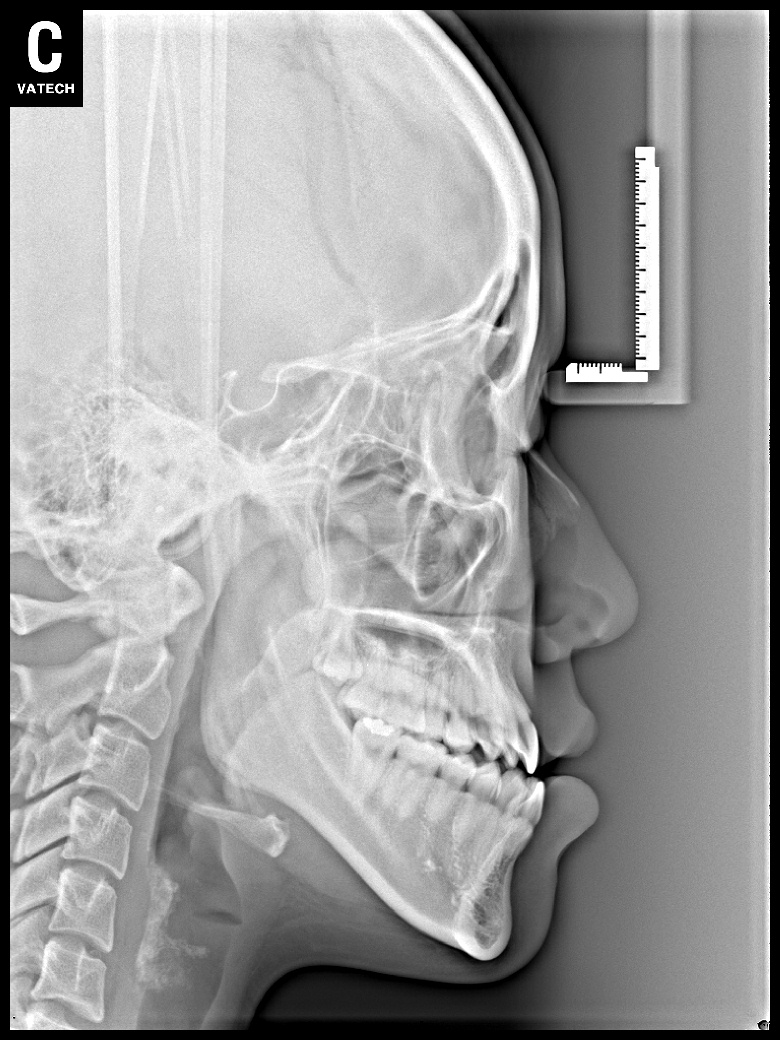

치료 후 사진입니다.